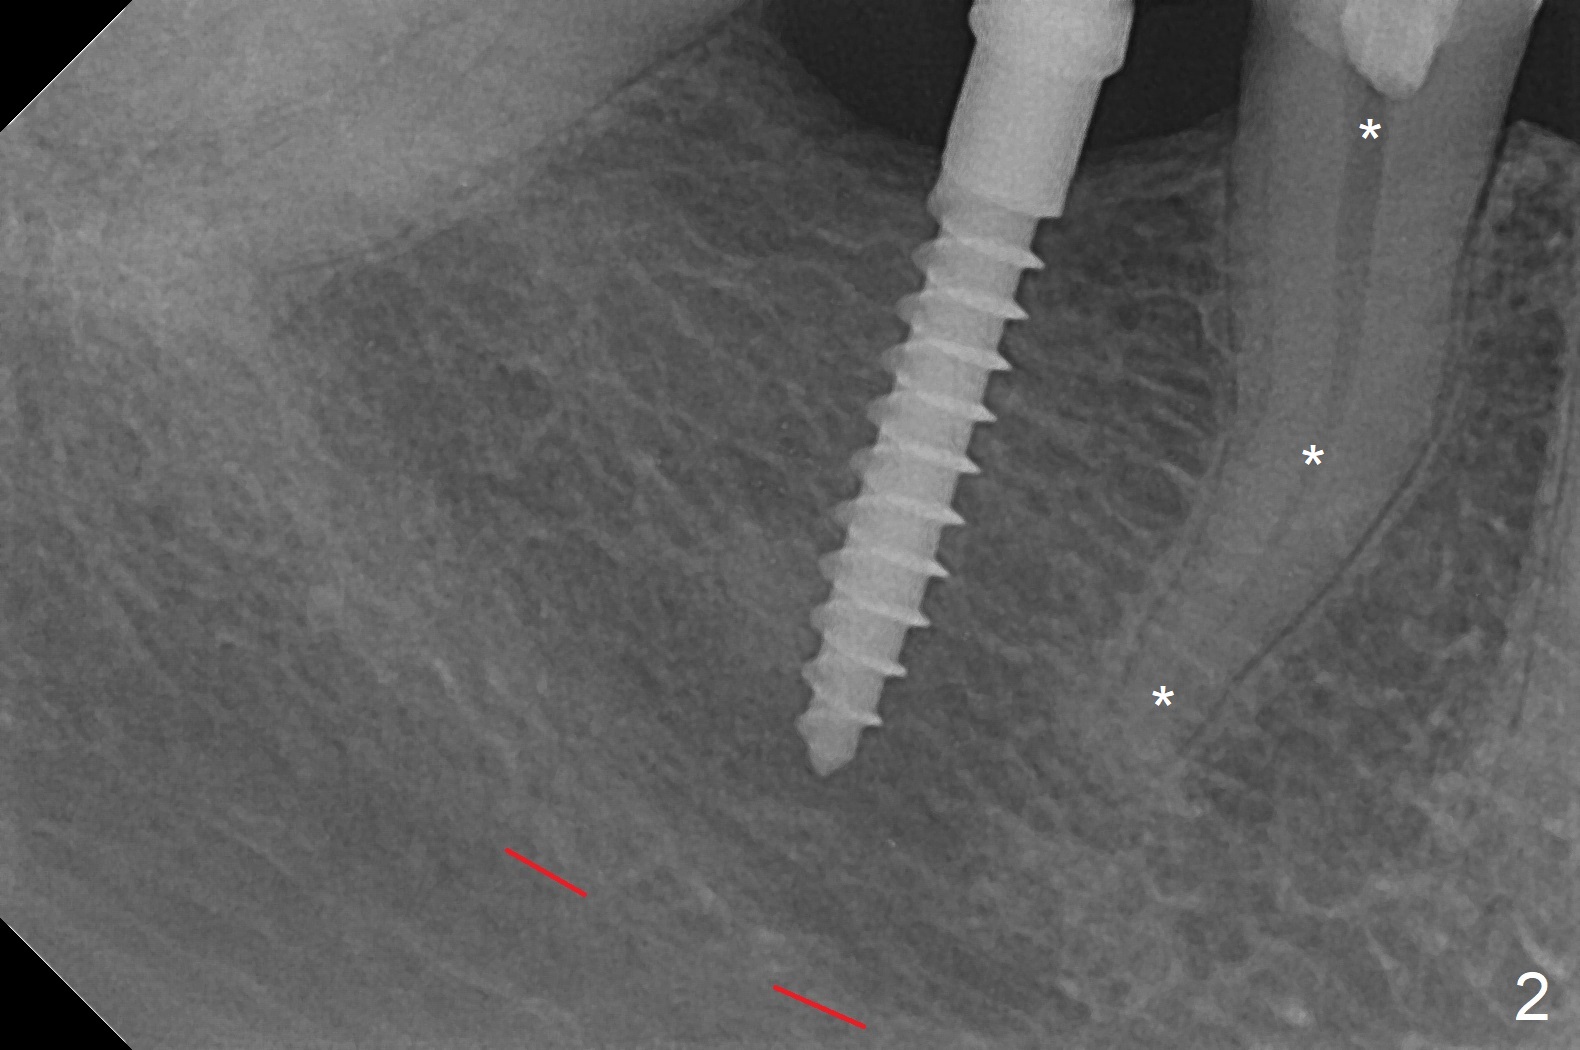

The mesial surface of the tooth #31 is reduced prior to osteotomy (Fig.1 >) so that the mesiodistal width of the edentulous area is 4.5 mm. An incision is made instead of tissue punch because of the narrow keratinized gingiva. The potential osteotomy site happens to have nonkeratinized tissue. When a 2.5x12(2) mm 1-piece implant is placed, it is close to the curved root of the 2nd premolar (Fig.2 *). Because of apparently sufficient clearance from the Inferior Alveolar Canal (Fig.2 red dashed line), the implant is placed ~ 1 mm deeper later. After suturing, periodontal dressing is applied. At patient's request, a provisional is fabricated with occlusal clearance 26 days postop. The occlusal surface of the provisional perforates 3.5 months postop with the provisional having pressed the gingiva, which is consistent with crestal bone loss (Fig.3). There appears no bone loss 3 months post cementation (Fig.4). There is minimal bone loss 11 months post cementation; in fact the bone density around the coronal portion of the implant increases (Fig.5).